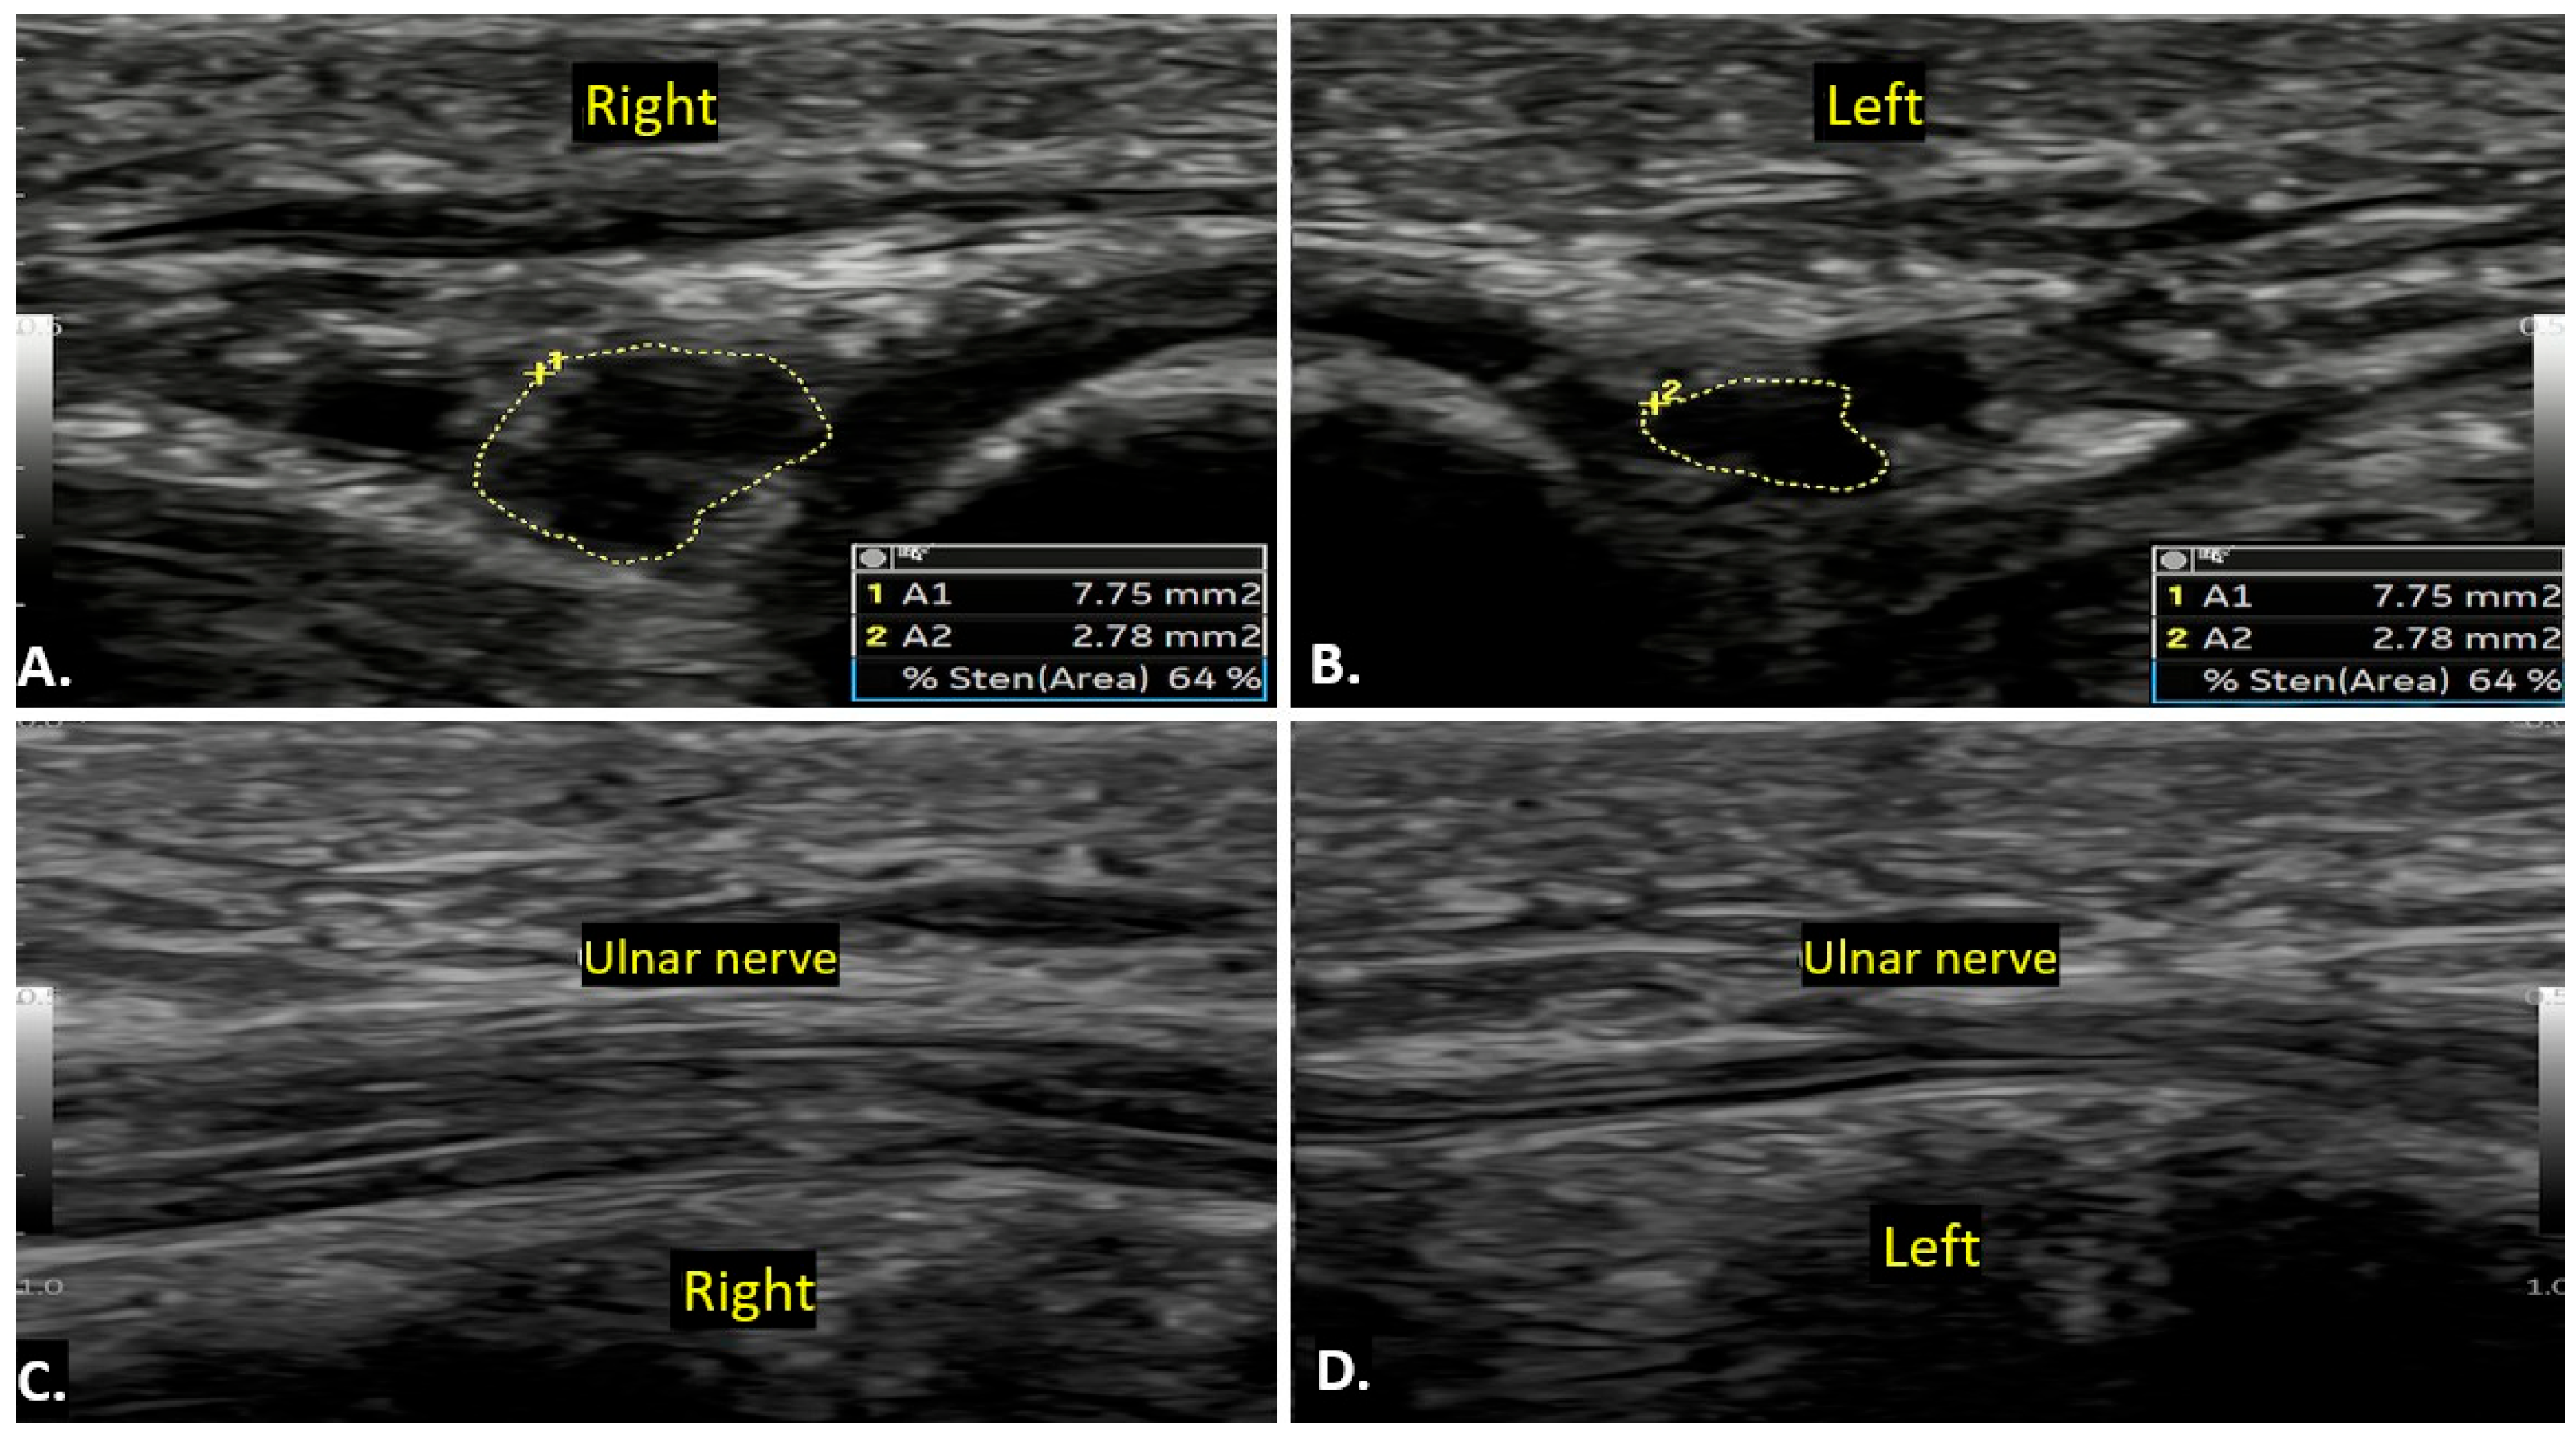

| Idiopathic Ulnar Neuropathy | Ulnar nerve swelling/thickening with loss of normal fascicular pattern. No compressive lesion. | Increased T2 signal in the affected nerve segment, indicating oedema or inflammation. |